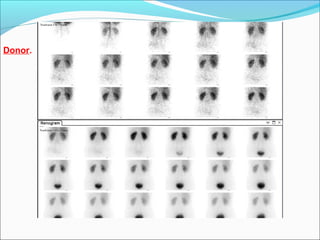

Donor.